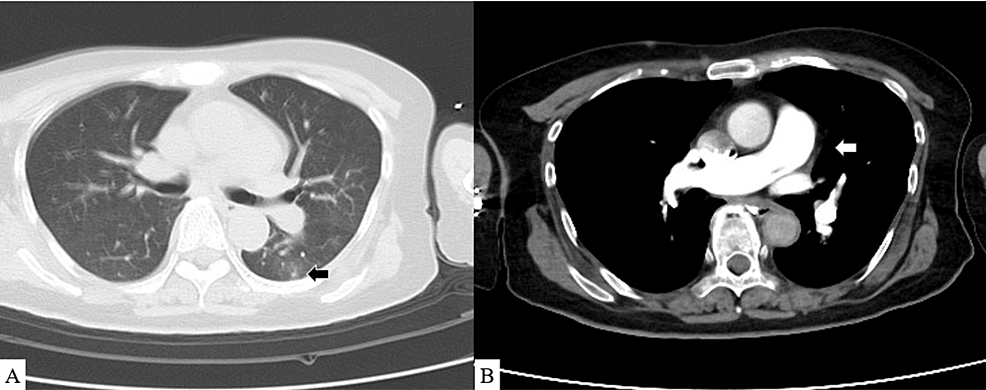

This case report is from a patient who died 15 days after onset of the disease.

A 61-year-old female with no relevant medical history presented to a hospital with sudden dyspnea. She received a Pfizer-BioNTech BNT162b2 mRNA injection two days before onset.

Contrast-enhanced CT showed no obvious contrast deficit in the pulmonary artery. Her hemodynamics deteriorated during the examination, leading to cardiac arrest. The patient was treated with venoarterial extracorporeal membrane oxygenation (VA-ECMO) via the femoral artery and vein, and her heartbeat resumed. She was transferred to our hospital for further treatment.

Blood tests revealed an elevated inflammatory response and liver and renal dysfunction.

COVID-19 vaccine-related myocarditis was suspected given sudden post-vaccine severe cardiac decompensation, and steroid pulse therapy and high-dose gamma globulin treatments were initiated.

Nitric oxide therapy for pulmonary hypertension was initiated, and an Impella heart pump fitted.

A myocardial biopsy was performed as well. On the seventh day, the flow through the Impella heart pump dropped and could not be maintained despite the reduction in the ECMO flow. The heart pump was removed. Transesophageal electrocardiography showed further RV enlargement and LV collapse.

This seemed insufficient for blood flow from the right to the left heart system. A myocardial biopsy revealed no significant inflammatory cellular infiltrates or evidence of amyloidosis or sarcoidosis. Chest radiography revealed severe pulmonary congestion. Follow-up CT showed the worsening of the lung field consolidation, and contrast defects of the pulmonary arteries remained absent.